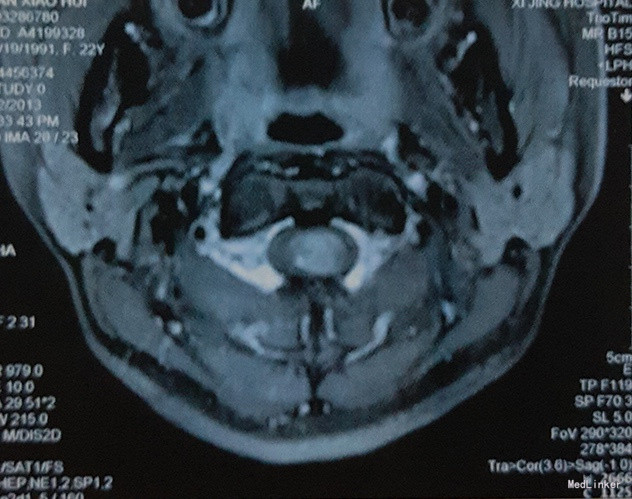

体格检查:左上肢肌力III级,右上肢及双下肢肌力IV级,肌张力降低。左上肢无法上举,右上肢运动正常。左上肢肘关节至肢端浅感觉消失,肘关节以上浅感觉减退;右上肢浅感觉减退,双下肢及躯干深浅感觉未见明显异常。心肺腹体检无明显异常。 影像学:全脊髓MRI结果:延髓-C5椎体平面颈髓稍增粗,可见等T1,等长T2信号,增强扫描均匀强化,下方脊髓可见囊性长T1,长T2信号,下方病灶延伸至T8平面,T9-L1平面脊髓T2信号增高,无明显强化。考虑:1、延髓-C5椎体平面髓内囊实行占位性病变,强化明显,考虑星形细胞瘤可能性大;2、其下方至T8椎体平面脊髓空洞形成。3、T8-L1椎体平面脊髓变性。